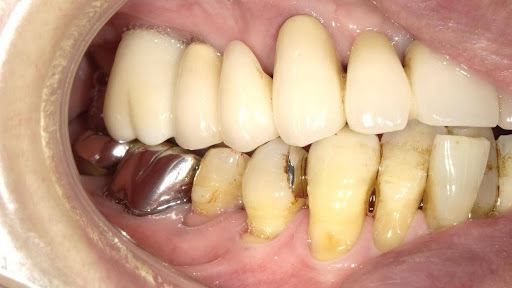

Before

枚方市のインプラントの症例

M・I 様 女性 70代

症状としては、左下56は、歯周病で欠損したと考えられるが、かなりの骨欠損をともなっていた。左上456に関しては、動揺が大きく、炎症が起き、排膿、および、歯性上顎洞炎を起こしていた。

治療法としては、動揺がひどくなってきて、炎症の症状もあったため、左上56の抜歯を希望。インプラント治療をその後、希望したため、左上4に関しては抜歯即時埋入。左上6に関しては、既存骨1から2mmでインプラント治療が厳しい状態であったが、グラフトレスサイナスリフトを行い、治療期間5か月はかかるということを説明して、インプラント埋入をおこないました。その後、2か月半後、大幅に骨が欠損している下顎56に対して、ショートインプラントを使用して、下顎神経の損傷を避けて、インプラント埋入を終えています。その後2か月後に光学印象で印象を行い、上顎刺億456歯、3ユニットのジルコニアブリッジを装着。下顎左側56に関しては、骨欠損が大きいため、歯冠長がだいぶ長くなるため、ジルコニアの連結冠を装着して治療を終えた。

治療結果は、上顎6に関しては、既存骨が少なく、厳しい治療ではありましたが、5か月で治療を終え、患者様の負担を最小限に抑えるができたと考えます。(従来のサイナスリフトでは、このようなケースでは1年以上、1年程度の治療期間がかかるか、治療が不可能と言われるケースだと考えます。)また、下顎は骨欠損が大きく、下歯槽管のリスクが起きることが考えられますが、ショートインプラントを使用することで安全に治療を行うことができました。

治療の期間・回数:治療期間5か月(上顎456 3ピースブリッジの治療は5か月(上顎既存骨が2mm程度しかなく、骨結合に時間がかかるケースであったために、5か月の治療期間が必要であった。)(左下56に関しては2か月半で治療を終えています。)治療回数は、13回。

治療の価格:1,474,000円(税込)

治療費の内訳:左上46および左下56のインプラント基本料(フィックスチャー及び手術費用、投薬費用、レントゲン費用、インプラント上部費用(アバットメントおよびジルコニアクラウンの費用用)330000円(税込み)×4本分 1320000円(税込)。左上5ジルコニアポンテック費用88000円(税込)。オプション費用、左上4抜歯即時埋入加算(人工骨費用を含む)+グラフトレスサイナスリフト費用 33000円(税込)、左上6グラフトレスサイナスリフト費用 33000円(税込)

治療のリスクや副作用:手術後に、痛みや腫れ、出血、合併症などを引き起こす可能性があります。噛む感覚がご自身の歯と異なる場合があります。見た目がご自身の歯と異なる場合があります。手術後にメインテナンスを継続しないと、インプラントが抜け落ちる可能性があります。